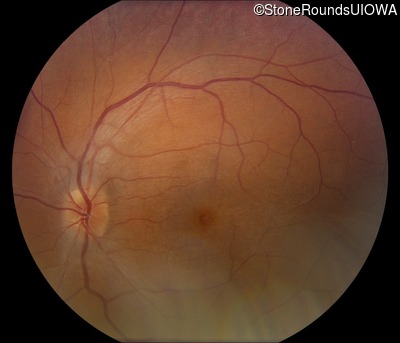

Fundus Photography - Left - 20/50 -3